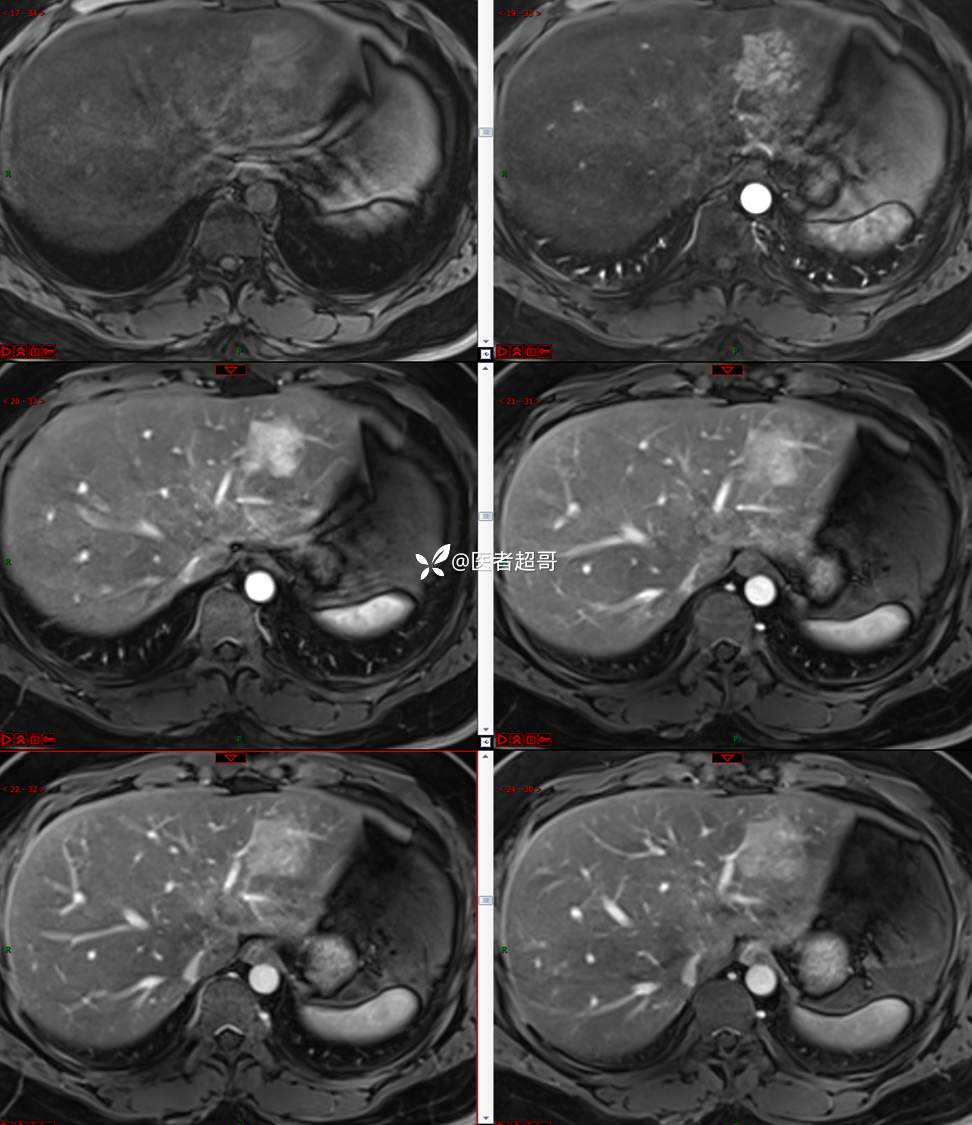

【影诊笔记685】男,31y,发现肝占位性病变5天就诊,请诊断分析,有病理结果!

主 诉:发现肝占位性病变5天。

现病史:患者缘于5天前体检时发现肝占位性病变,未予以特殊处置。现患者为求系统诊治就诊于我院,行普美显提示:肝左叶富血供占位,请结合临床及其他检查,肝多发血管瘤,脂肪肝,肝囊肿,请结合临床。门诊以“肝占位性病变”收入我科。病程中,饮食睡眠可,二便可,近期体重未见明显变化。